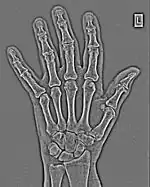

FFTs can also be calculated in two-dimensions to give results such as those in Figure 1.27. Since Fourier analysis generates results in terms of both positive and negative spatial frequencies, these can be plotted in the form of a 2D image so that the maximum frequency lies at the origin and those for the horizontal and vertical directions are shown increasing towards that origin. The modulation at different spatial frequencies is represented using a grey-scale. Low frequency bands can be seen along the horizontal axis in the figure, for example, representing the horizontal periodicity of image data from the fingers, while finer bands along the y-dimension are indicative of a periodicity of image data from the various metacarpophalangeal joints. Higher frequency features can also be seen running diagonally in this 2D-FFT, representative of the trabecular structure of the bones, for example.

The essence of this approach is that it can be used to produce a range of image processing effects by enhancing and/or suppressing features in the 2D-FFT and then converting the result back into the spatial domain using the IFT, as illustrated in Figure 1.28. Such image manipulations are considered in more detail in a later chapter. Note that the form of image processing demonstrated in the figure is for purely illustrative purposes and bears no direct medical significance.

![]() Fig. 1.28(a): A radiograph of the wrist. | ![]() Fig. 1.28(b): The wrist radiograph processed by attenuating periodic structures of size between 1 and 10 pixels. |

![]() Fig. 1.28(c): The wrist radiograph processed by attenuating periodic structures of size between 5 and 20 pixels. | ![]() Fig. 1.28(d): The wrist radiograph processed by attenuating periodic structures of size between 20 and 50 pixels. |